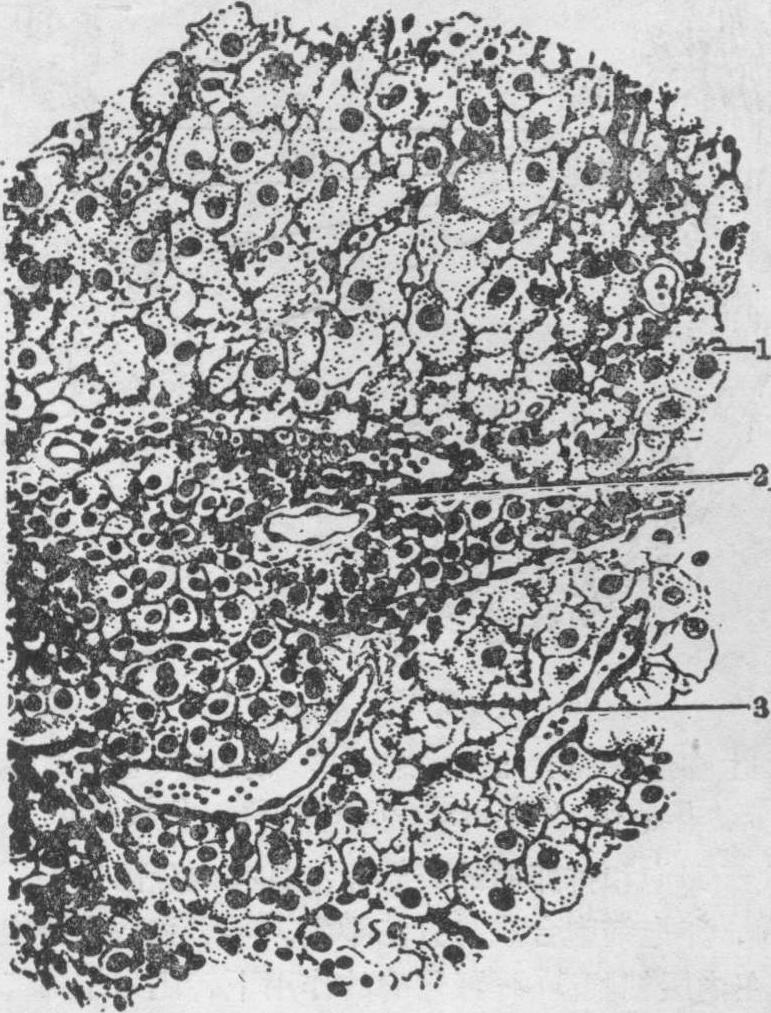

月经黄体 成熟卵泡排出的卵如未受精,所形成的黄体为月经黄体。排卵后残留在卵巢内的卵泡壁塌陷形成皱襞,伴有内膜层毛细血管破裂,以至卵泡腔内充满一些液体及血液,这种结构称为血体。随后,卵泡的基膜消失,血管和结缔组织侵入粒层,粒层细胞和内膜层细胞在黄体生成素作用下发育成黄体细胞,组成黄体。月经黄体的直径为1.5~2cm。由粒层细胞转变成的黄体细胞称为粒黄体细胞(图1)。细胞体积较大,胞质着色浅,充满了细小脂滴和黄色的脂色素。电镜下胞质内有大量滑面内质网和少量扁平囊状的粗面内质网,线粒体具有管状嵴(图2)。由内膜层细胞转变成的黄体细胞称膜黄体细胞(图1),体积较粒黄体细胞小,胞质染色稍深,位于粒黄体细胞外围,结构和粒黄体细胞相似。黄体除由粒黄体细胞产生大量孕激素外,还在两种黄体细胞的协同作用下产生一定量的雌激素和雄激素。月经黄体维持2周后退化,产生的孕激素量下降,细胞逐渐变小,发生脂肪变性,最后为白体替代。白体为致密结缔组织,可存在数月,最后消失。

图1 黄体

1.粒黄体细胞 2.膜黄体细胞 3.血管